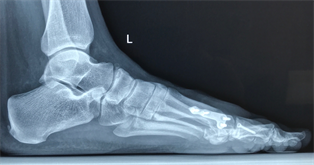

Figure 18. Patient Nr. 4. Bilateral moderate hallux valgus.

Figure 19. Patient Nr. 4. Side view left foot.

Figure 20. Patient Nr. 4. Side view right foot.

Figure 21. Patient Nr. 4. 5 years after bilateral correction. Outpatient. Immediate full weight bearing.

Figure 22. Patient Nr. 4. Side view of the left foot shows the plantarization of 2 mm.

Figure 23. Patient Nr. 4. Side view of the right foot shows the plantarization of 2 mm.